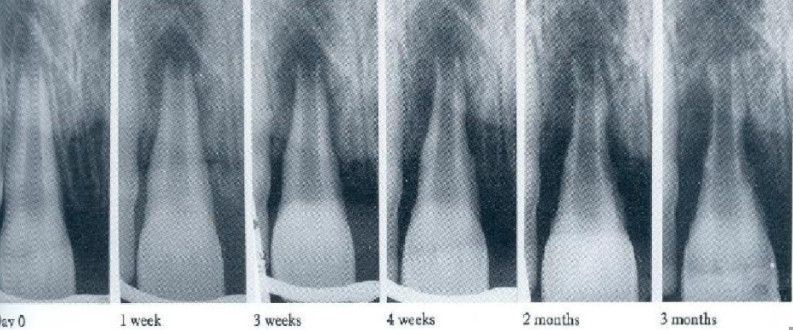

6、什么时间能确定牙髓源性根尖周病变正在愈合?

图:6 牙髓源性根尖周病变的 愈合时间存在显著差异,因此 必须长期随访。